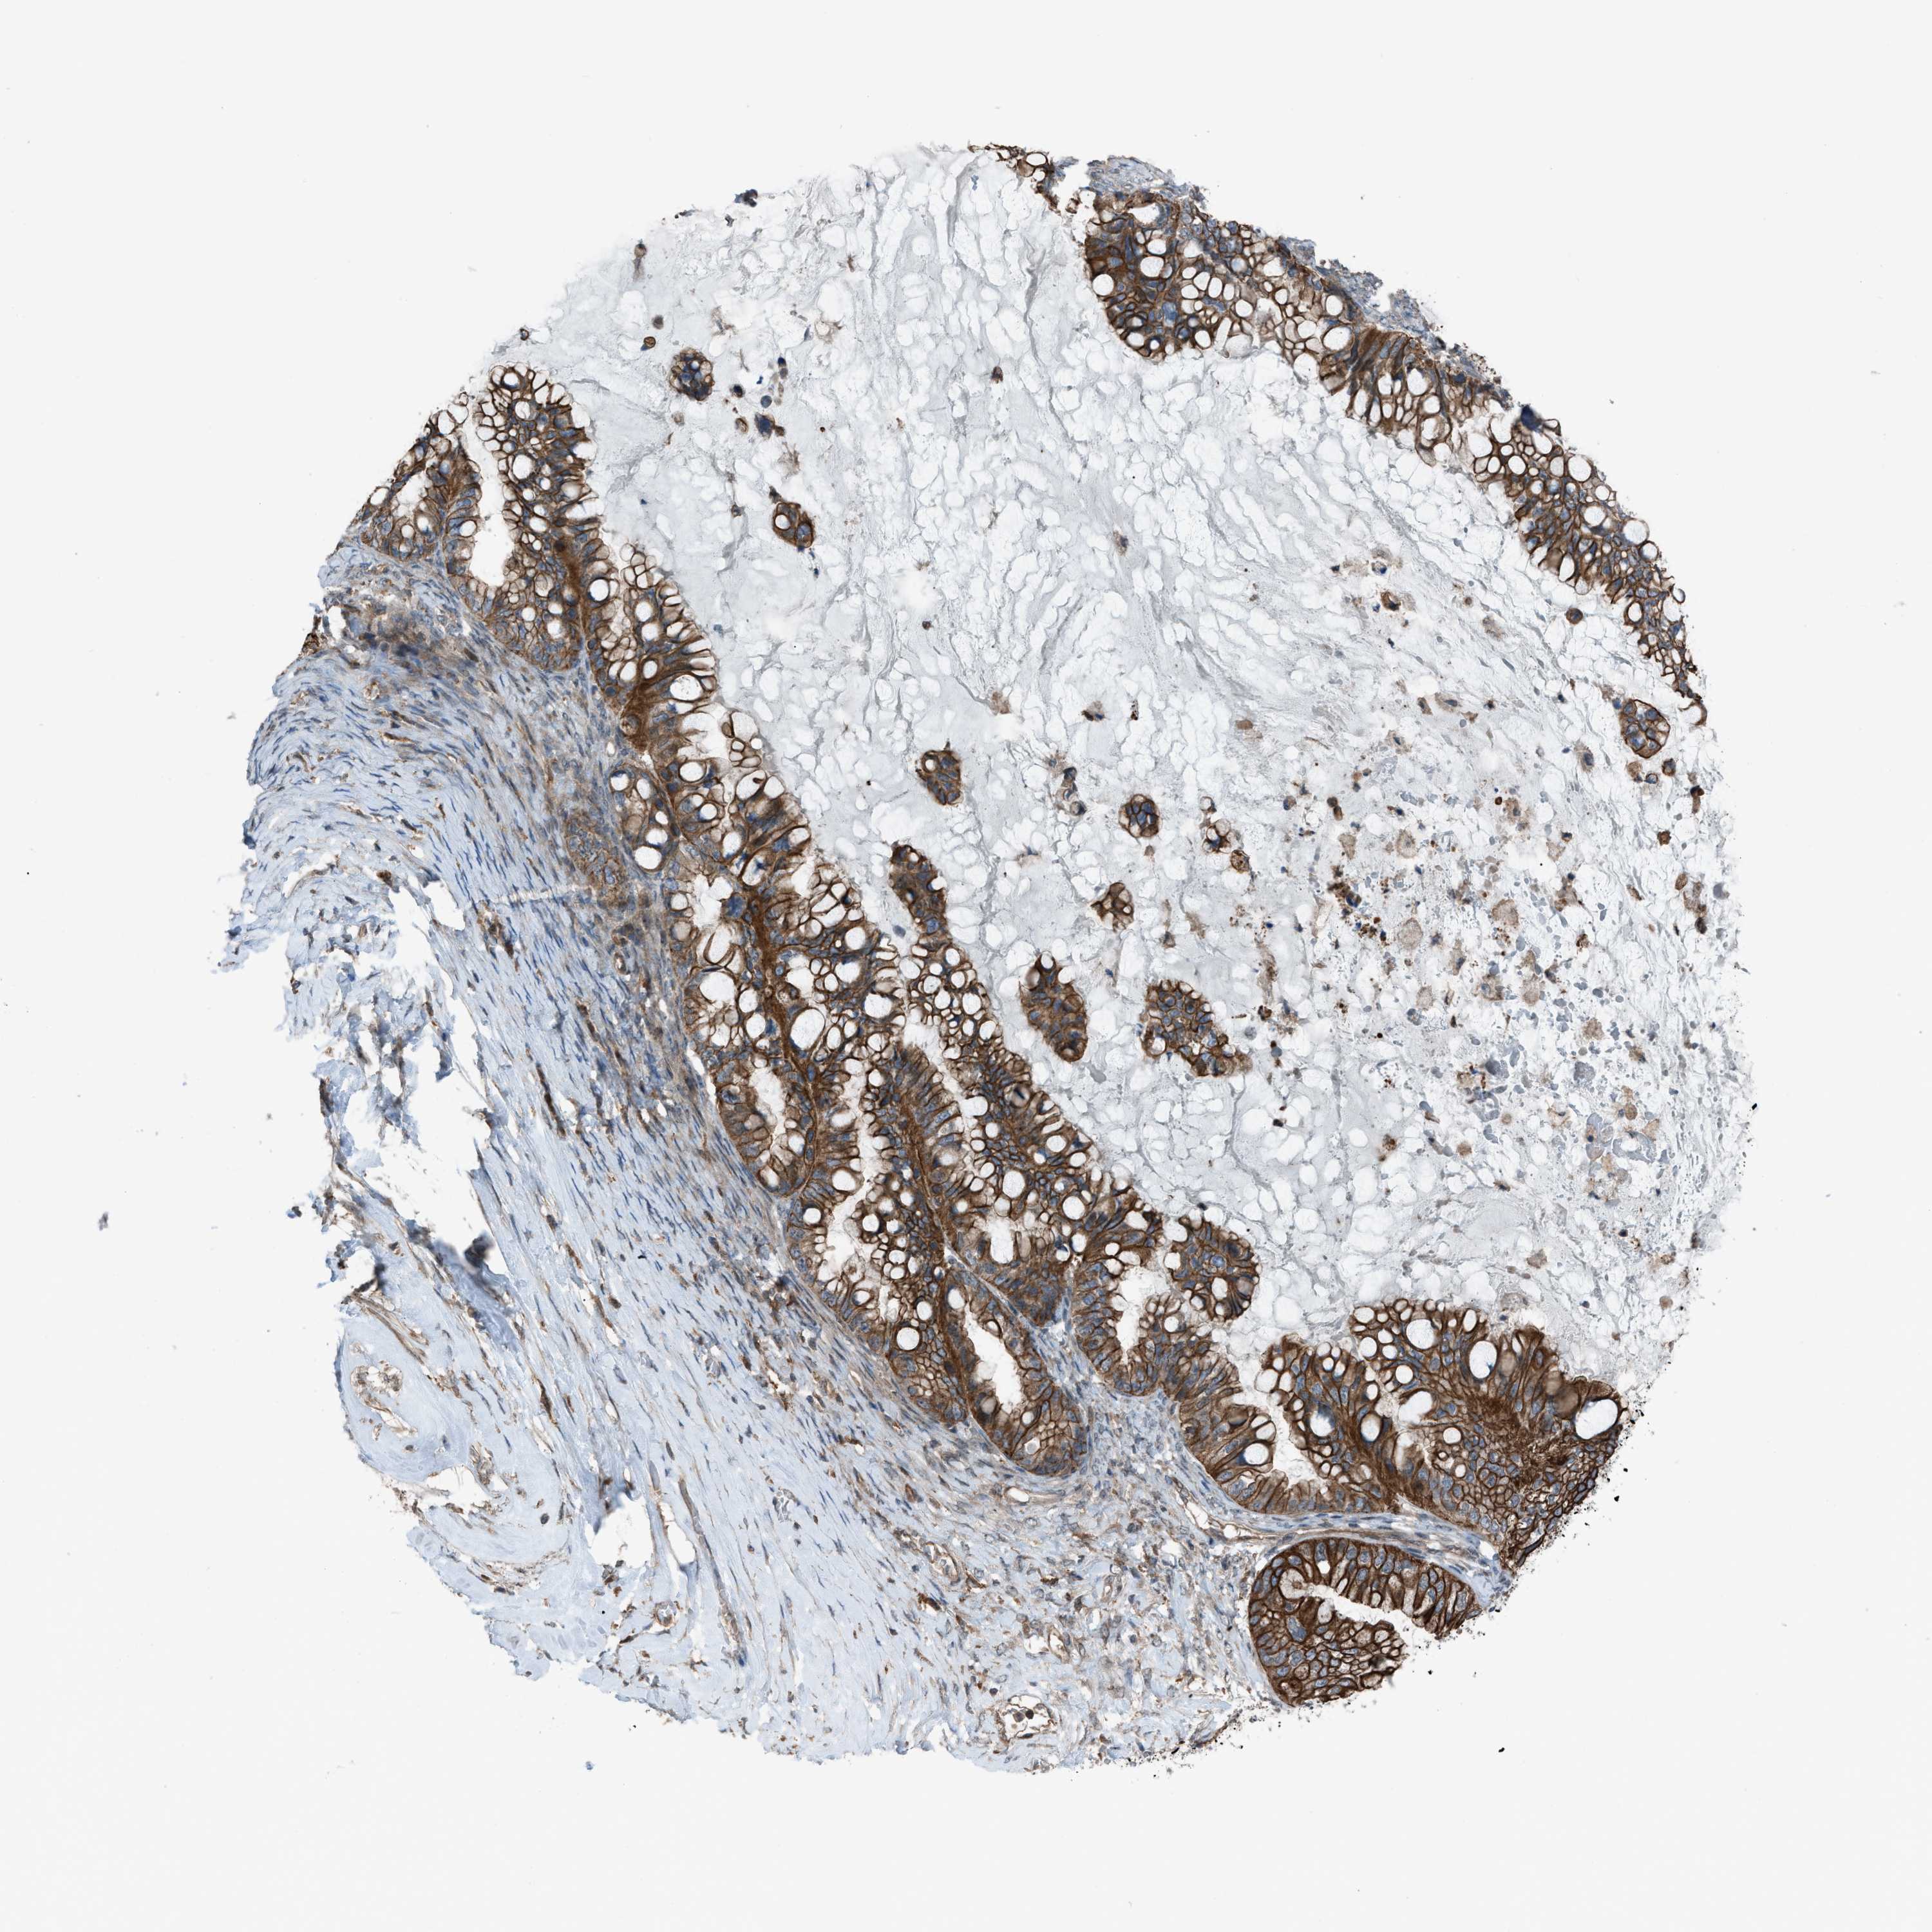

OVARIAN CANCER - Protein expressioni

A mouse-over function shows sample information and annotation data. Click on an image to view it in a full screen mode. Samples can be filtered based on level of antibody staining by selecting one or several of the following categories: high, medium, low and not detected. The assay and annotation is described here.

Note that samples used for immunohistochemistry by the Human Protein Atlas do not correspond to samples in the TCGA dataset.

Antibody stainingi

Antibody staining in the annotated cell types in the current human tissue is reported as not detected, low, medium, or high, based on conventional immunohistochemistry profiling in selected tissues. This score is based on the combination of the staining intensity and fraction of stained cells.

Each image is clickable and will lead to virtual microscopy that enables deeper exploration of all samples and also displays staining intensity scores, fraction scores and subcellular localization as well as patient and tissue information for each sample.

Antibody HPA015323

Antibody HPA015810

Carcinoma, NOS

Cystadenocarcinoma, serous, NOS